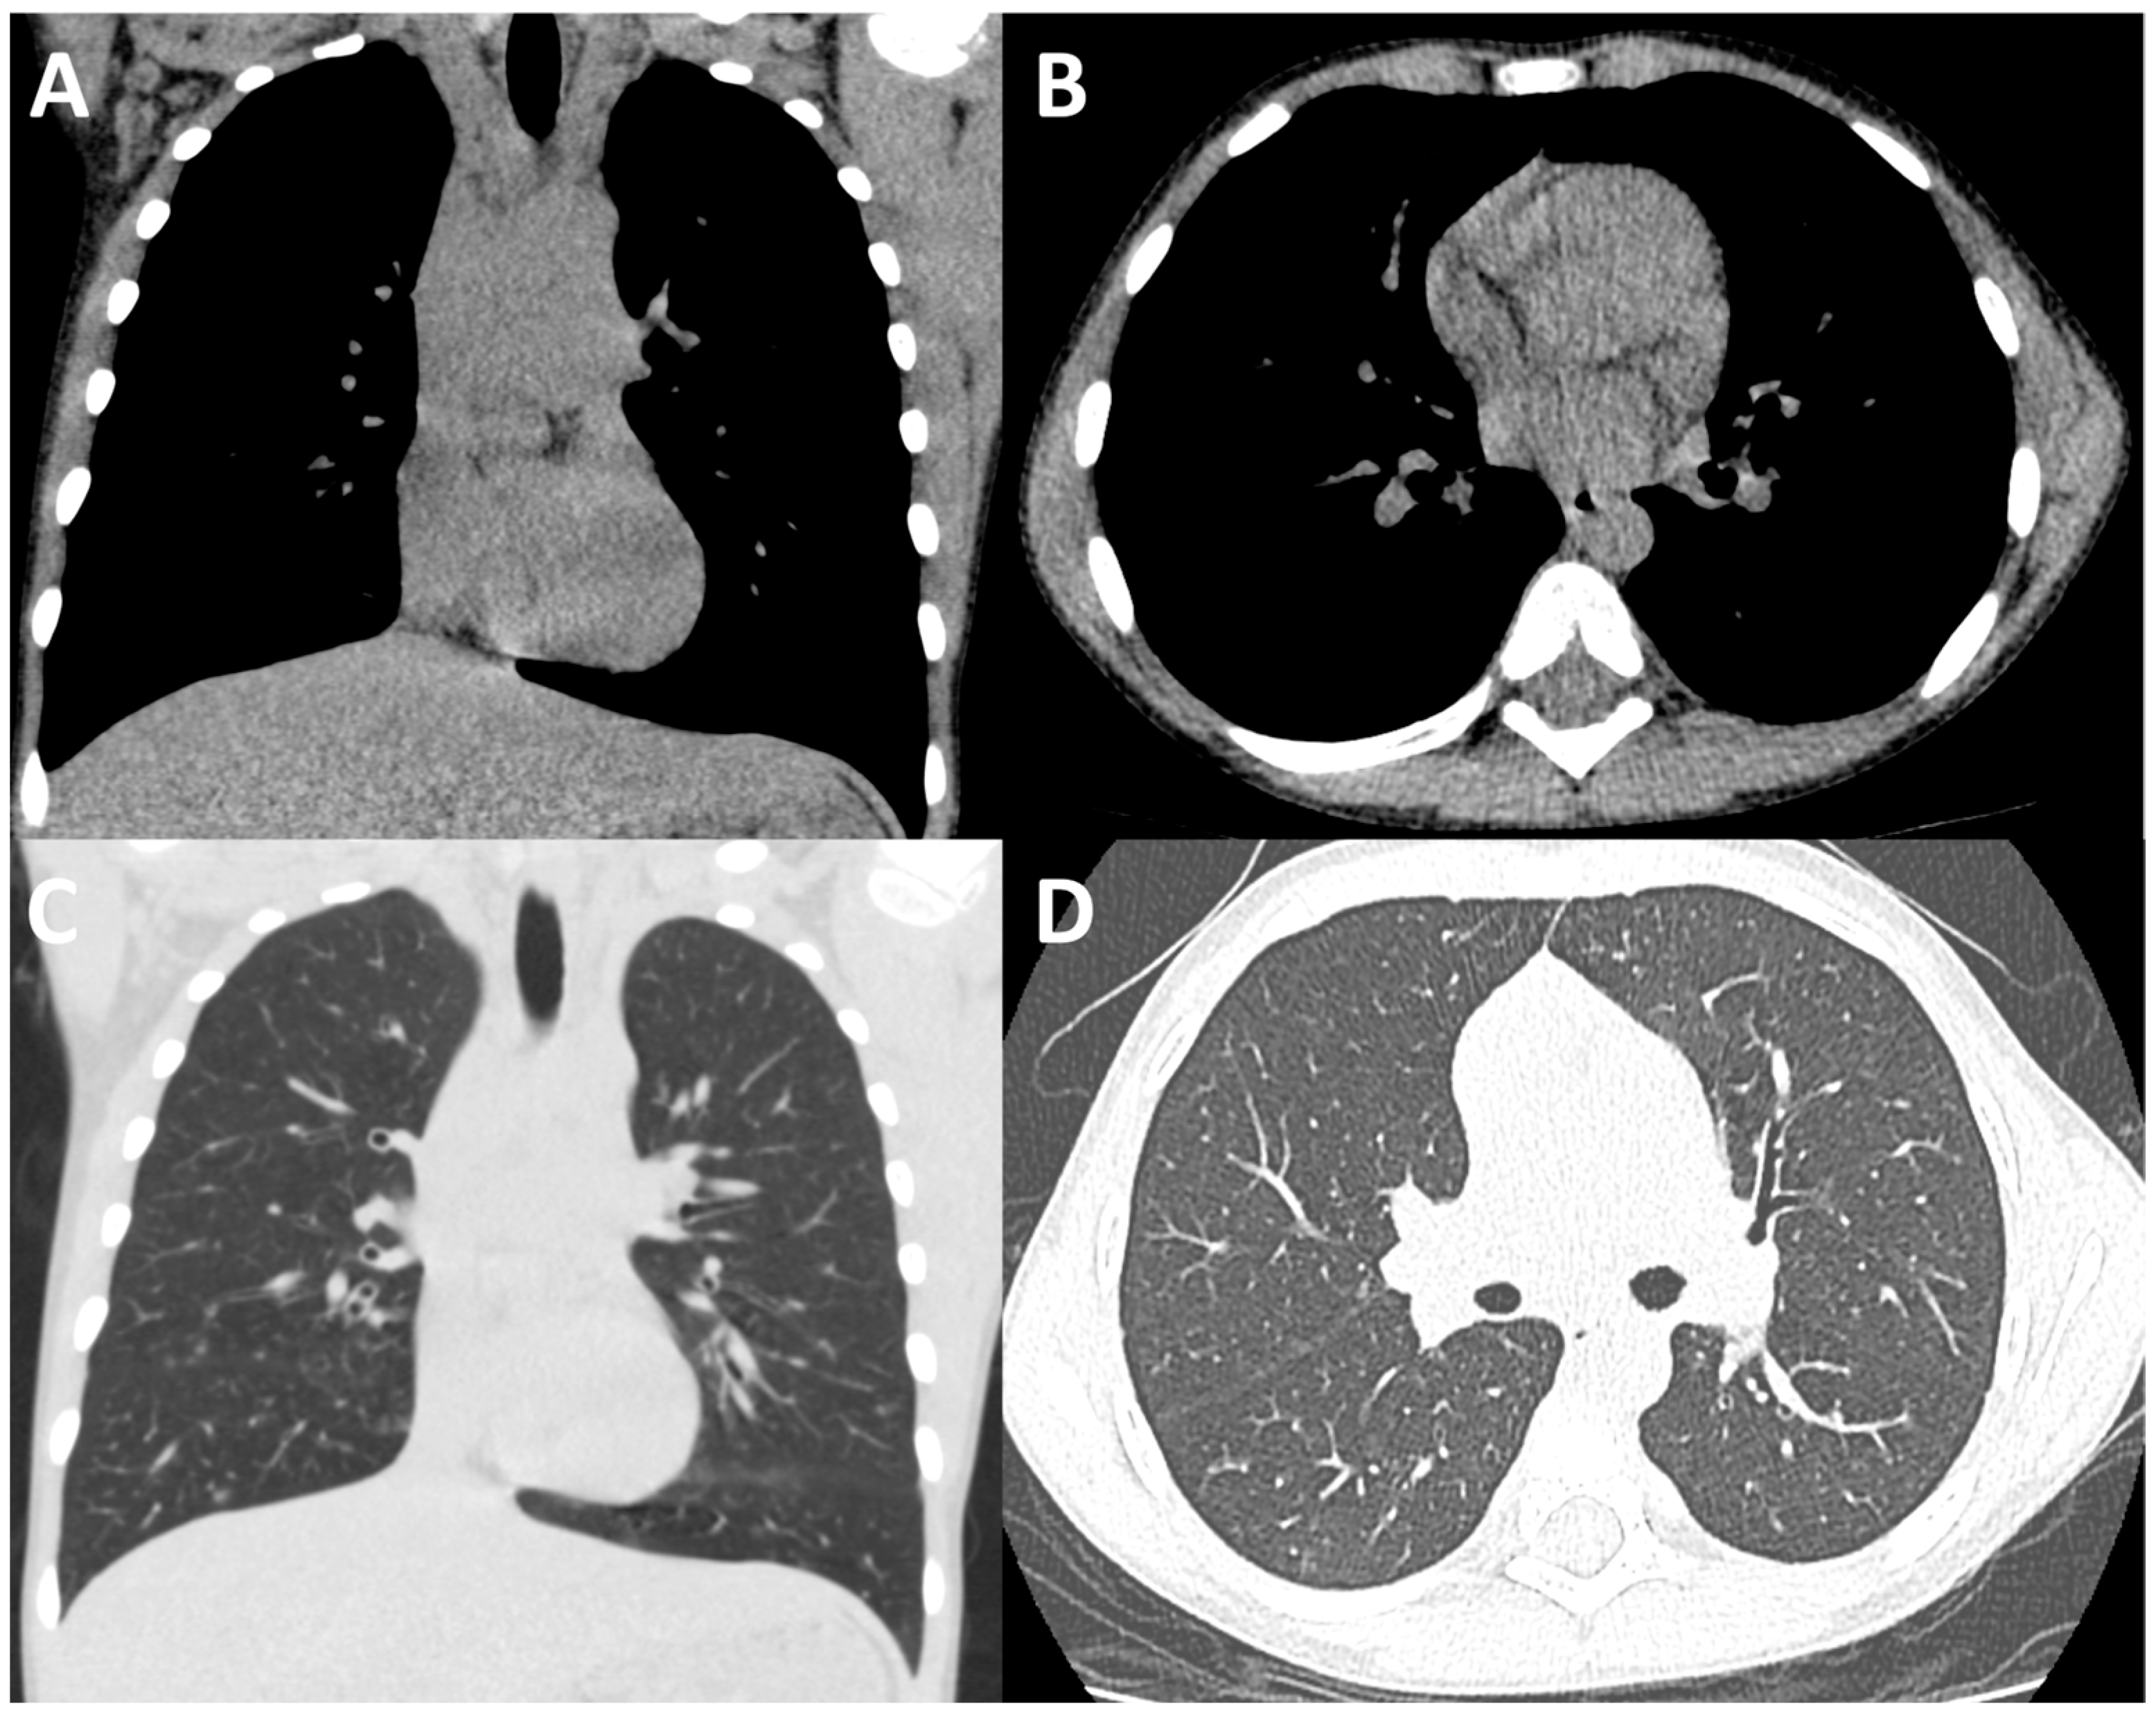

Figure 1.

Conventional-dose CT of the thorax. Coronally (A,C) and axially reconstructed (B,D). Conventional-dose CT of the thorax images in soft tissue (A,B) and lung windows (C,D) in a paediatric male CF patient performed during an acute hospital admission. The dose length product (DLP) for this examination was 39.77 mGy*cm.